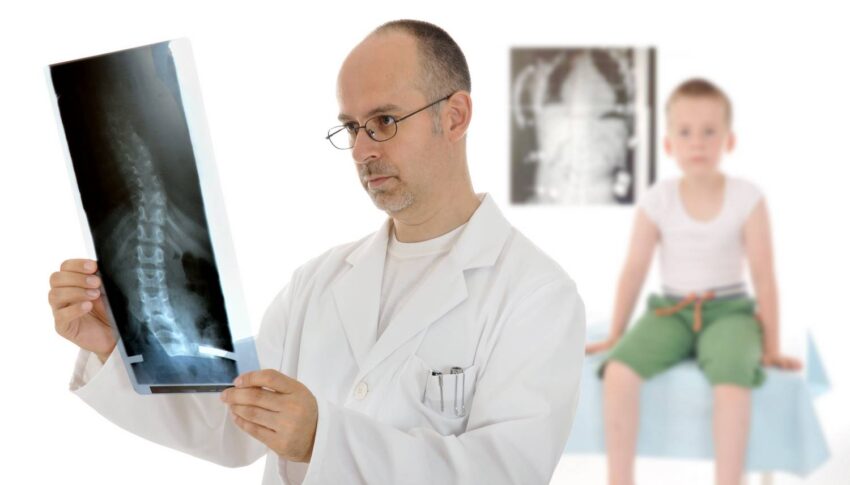

Ortopeda w Szczecinie

Ortopeda w Szczecinie to lekarz specjalizujący się w diagnostyce, leczeniu i rehabilitacji schorzeń układu ruchu, takich jak urazy, choroby zwyrodnieniowe stawów, choroby kości, wady postawy oraz różnego rodzaju deformacje. Ortopeda…

Co robi ortopeda?

Co robi ortopeda? Wiele osób ma problemy z narządem ruchu i czasami nie wie do jakiego lekarza się udać. Jest to dziedzina medycyny, którą zajmują się chirurdzy plastyczni. Oprócz leczenia…